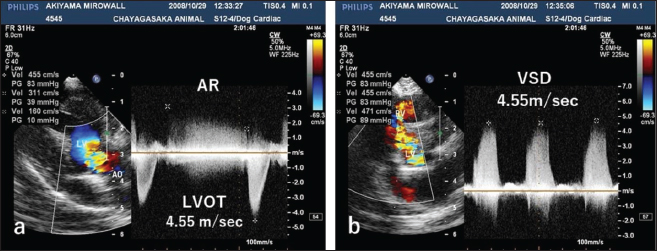

Auscultation revealed a heart rate of 150 beats/minutes and a grade 4/6 systolic murmur in the precordial region near the sternum. Electrocardiography revealed a mean electrical axis of +82º and a mitral P wave in the II, III, and aVF leads. Thoracic radiography showed moderate heart enlargement (vertebral heart score, 10 vertebrae; cardio-thoracic ratio [CTR]: 70%) and increased opacity of the pulmonic field. B-mode echocardiography revealed a small polypoid mass at the dorsal part of the interventricular septum below the aortic valve (Fig. 1a). Two areas of flow acceleration were evident, leading to the mosaic pattern on colour flow Doppler echocardiography: one due to a membranous VSD of 3.17 mm in diameter and the other due to LVOT obstruction caused by the mass (Fig. 1b). In the continuous-wave Doppler (CWD) mode, the LVOT blood flow velocity was 4.55 m/seconds, with a calculated systolic pressure gradient (ΔP) of 83 mmHg between the left ventricle (LV) and aorta (Fig. 2a), and the VSD blood flow velocity was 4.55 m/seconds, with a calculated systolic ΔP of 83 mmHg between the LV and right ventricle (RV) (Fig. 2b). Aortic regurgitation (AR) (Fig. 2a) was also observed. In the CWD mode, the AR blood flow velocity was 3.11 m/seconds, with a calculated diastolic ΔP of 39 of mmHg between the aorta and LV (Fig. 2a).

Fig. 2. CWD echocardiography of the right parasternal long-axis view. (a) The blood flow velocity in the left ventricular outflow tract (LVOT) was 4.55 m/seconds, with a calculated systolic pressure gradient (ΔP) of 83 mmHg between the LV and aorta (AO). The AR blood velocity was 3.11 m/seconds, with a calculated diastolic ΔP of 39 mmHg between the LV and AO. (b) The blood flow velocity in the ventricular septal defect (VSD) was 4.55 m/seconds, with a calculated systolic ΔP of 83 mmHg between the LV and RV. The peak velocity measurement of LVOT, AR, and VSD is not accurate, because of measurements taken using the “beard” instead of the “chin” (see “Study Limitations”).

Echocardiography is the best tool for the detection of intracardiac tumour, especially obstructive myxomas (Bright et al., 1990; Ori et al., 1994; Fernandez-del Palacio et al., 2011; Šimundić et al., 2019; Stack et al., 2021; Mellish et al., 2022). In the present case, auscultation, electrocardiography, and thoracic radiography were also useful. B-mode, colour (Fig. 1a, b), and CWD (Fig. 2a, b) echocardiography clearly revealed a small polyploid mass that moderately obstructed the LVOT, as well as AR and a membranous VSD. The VSD likely caused the AR.

For CWD echocardiography, Kyranis et al. (2018) identified the measurement site for peak velocities on Doppler wave to ensure the exact value is taken at the “chin” and not the “beard”. In this case (Fig. 2a and b), we measured the peak velocities at the beard, not the chin. Therefore, the exact volume appears to be slightly lower. However, this cannot be corrected because of a lack of original image data. On echocardiographic assessment of the LVOT, pulsed-wave Doppler (PWD) is used for LVOT flow evaluation when no flow acceleration is noted to accurately measure the specific velocity at the region of interest. When there is a fixed obstruction or dynamic obstruction (as is possible in this case owing to the mobile mass) leading to flow acceleration, then aliasing of PWD can occur, which forces us to use CWD for evaluation of the peak velocity and peak gradient (Koplitz et al., 2006). However, in our case, we did not obtain PWD data.